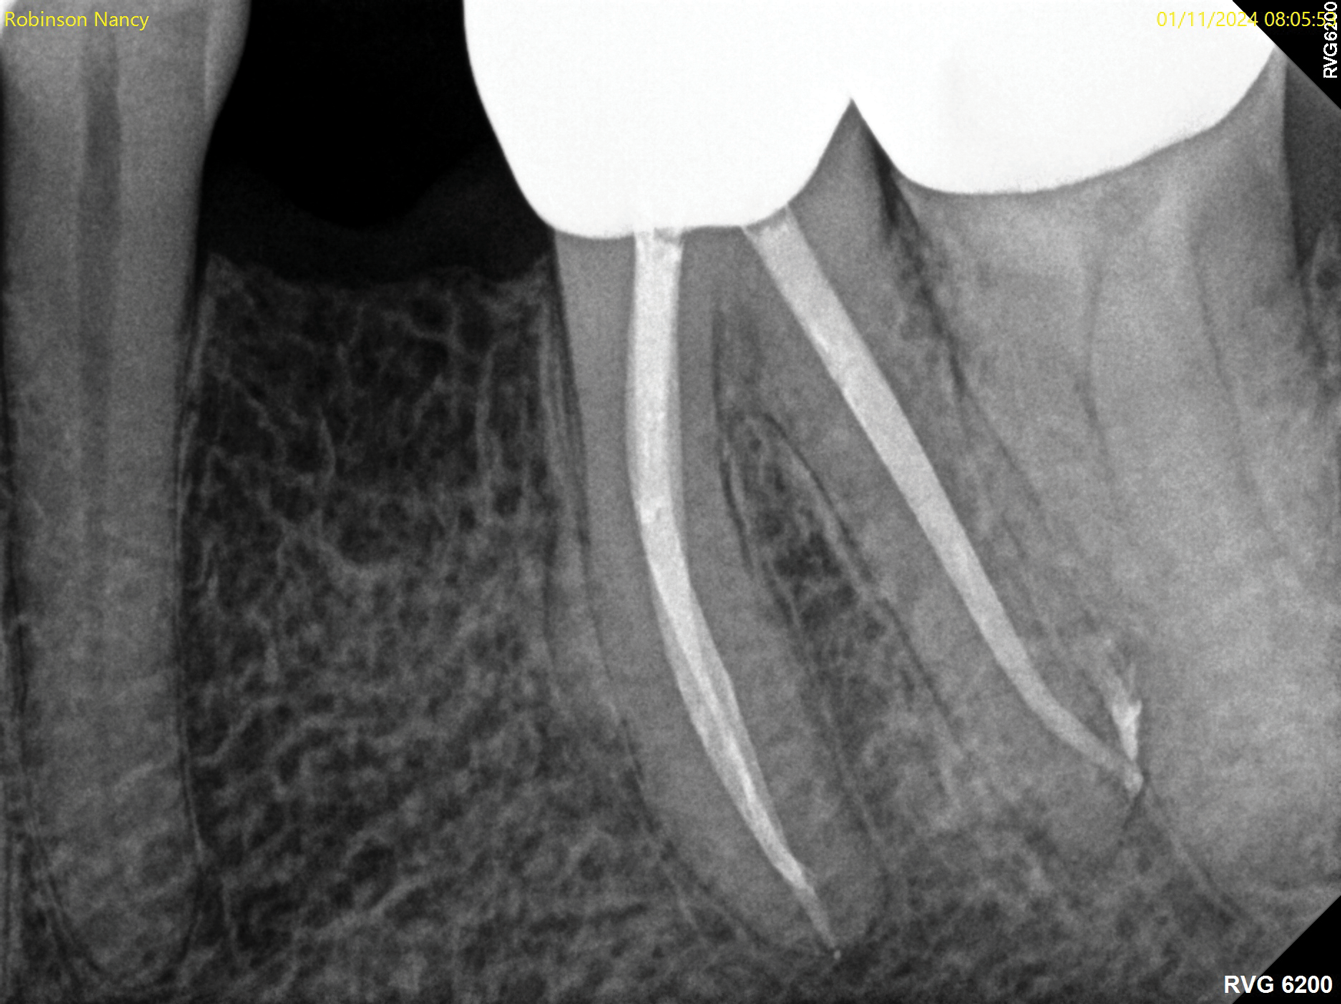

Fig 7. Identifiable inadequate NSRCT is associated with predictable RETX. Fig 6: Preoperative periapical radiograph showing AP, tooth No. 20. Fig 7. Postoperative periapical radiograph. Fig 8. Six-month follow-up periapical radiograph showing a significant decrease in size of the AP.

Figure 7

Fig 8. Identifiable inadequate NSRCT is associated with predictable RETX. Fig 6: Preoperative periapical radiograph showing AP, tooth No. 20. Fig 7. Postoperative periapical radiograph. Fig 8. Six-month follow-up periapical radiograph showing a significant decrease in size of the AP.

Figure 8

The quality of the initial NSRCT is inversely associated with RETX outcomes, with poorer quality initial treatment tied to more predictable retreatment (Figure 6 through Figure 8).23 Inadequate quality of the initial NSRCT (eg, untreated anatomy, under-instrumentation, ledged and underfilled canals, and overextended obturation) was associated with greater predictability following RETX. However, if clinicians cannot identify and correct the mistakes made in the previous root canal therapy, it becomes more challenging to improve treatment outcomes.23